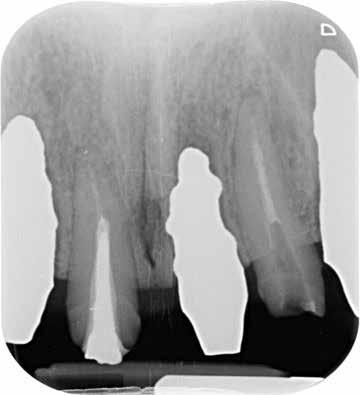

Ebben a cikkben egy 16 éves lánypáciens esetét szeretném bemutatni (1–7. képek)

A Pitts21-es fix készülékes kezelés során a harapásemelőket a felső nagyőrlő fogakra ragasztottuk, hogy a felső molárisok intrúziójával segítsék a harapás zárását (8. kép) Ún. keresztharapásos, majd később normál class 2-es gumihúzással (9–10. képek), továbbá az elülső fogakon alkalmazott ún. Rainbow harapás-záró gumihúzással (11. kép) korrigáltuk a jobb oldali teljes premolárisnyi distal-harapást, valamint az elülső nyitott harapást.

6 hónap után a nyitott harapás már nagyjából összezárásra került (12. kép)! A gumihordás a kezelés teljes hosszában folyamatos, éjjel-nappal, 22-24 órában az étkezések és az utánuk történő fogmosás kivételével.

A fix fogszabályozó készülék mindössze 16 hónapos kezelés után került eltávolításra! Páciensünk legnagyobb örömére állcsontműtét nélkül sikerült mind az arcesztétikai, mind a funkcionális rehabilitáció (13–18. képek)